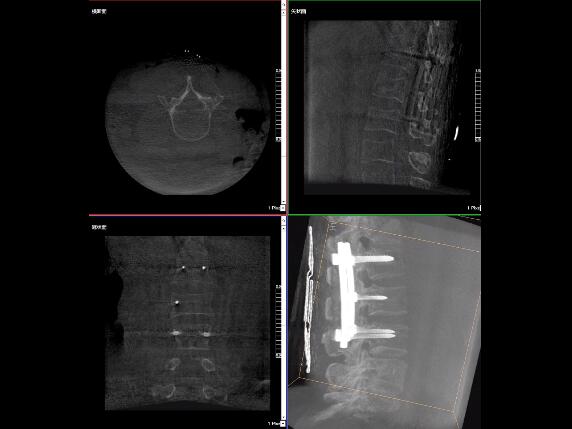

比如,醫(yī)生在做PKP(椎體成形術(shù))的時(shí)候,或者在置入螺釘?shù)臅r(shí)候,醫(yī)生需要在影像上看到螺釘打進(jìn)去的進(jìn)針點(diǎn)以及進(jìn)針的路徑。比如,我們在打腰椎的釘子時(shí)需要看到“貓眼”。我們只有把釘子完全打在“貓眼”里面,才能確保釘子打在了椎弓根里,所以對“貓眼”的顯影就非常重要。

“貓眼”指的是椎弓根在正位的投影。

最后我要強(qiáng)調(diào)一點(diǎn),以上我提到的“貓眼”,在二維的X光片上,醫(yī)生是靠經(jīng)驗(yàn)去判斷釘子是否打在椎弓根里,這個(gè)時(shí)候如果我們的設(shè)備再先進(jìn)一點(diǎn),診斷手段再多一點(diǎn),如果我們能夠把二維的影像轉(zhuǎn)換為三維的影像,可能就不會完全依賴醫(yī)生的經(jīng)驗(yàn)。

我們可以在三維的圖像中直觀的看到釘子到底在不在椎弓根里面,這樣可以指導(dǎo)我們準(zhǔn)確的進(jìn)針,指導(dǎo)我們進(jìn)行一場高質(zhì)量的手術(shù),可以起到事半功倍的效果,手術(shù)會簡單得多,病人的預(yù)后也會好得多。